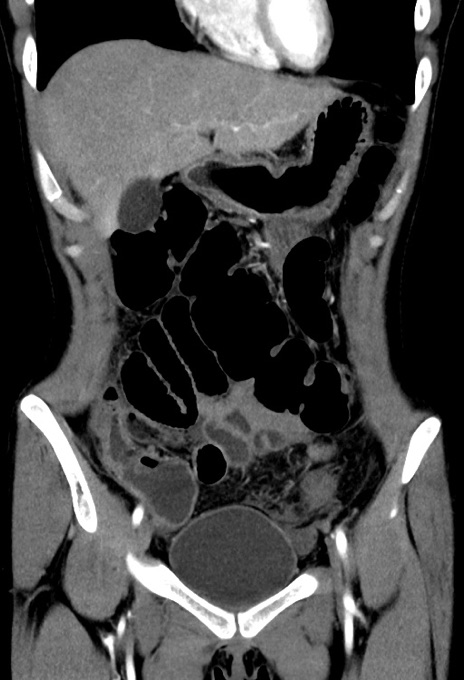

症例17(冠状断像)

【症例】20歳代女性

【主訴】嘔吐、下腹部痛

【現病歴】昨日夕食後に嘔吐し下腹部痛が出現。本日になっても嘔吐持続し改善しないため来院。

【身体所見】意識清明、BT 37.2℃、BP 108/67mmHg、腹部:平坦、やや硬、下腹部正中から右にかけて圧痛あり、反跳痛軽度あり、tapping pain(+)。

【データ】WBC 13600、CRP 14.94